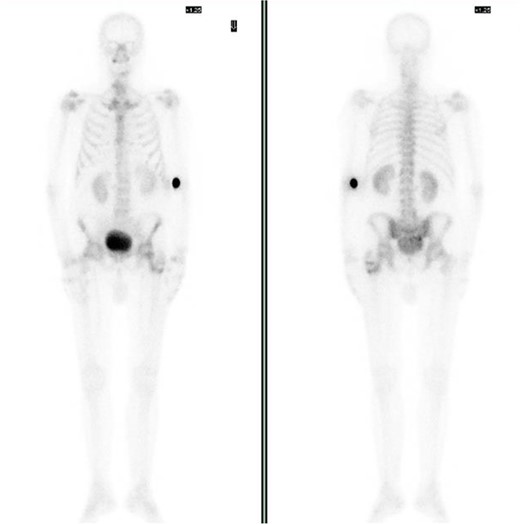

Bone scintigraphy of the entire skeleton, SPECT–CT of the pelvis (Fig. 2) and magnetic resonance imaging (MRI) was performed for surgical planning (Fig. 3A–C).

Bone scintigraphy of the entire skeleton with Tc99 and SPECT–CT. Highlighting of radioactive tracer in left proximal femur and sacrococcygeal region.